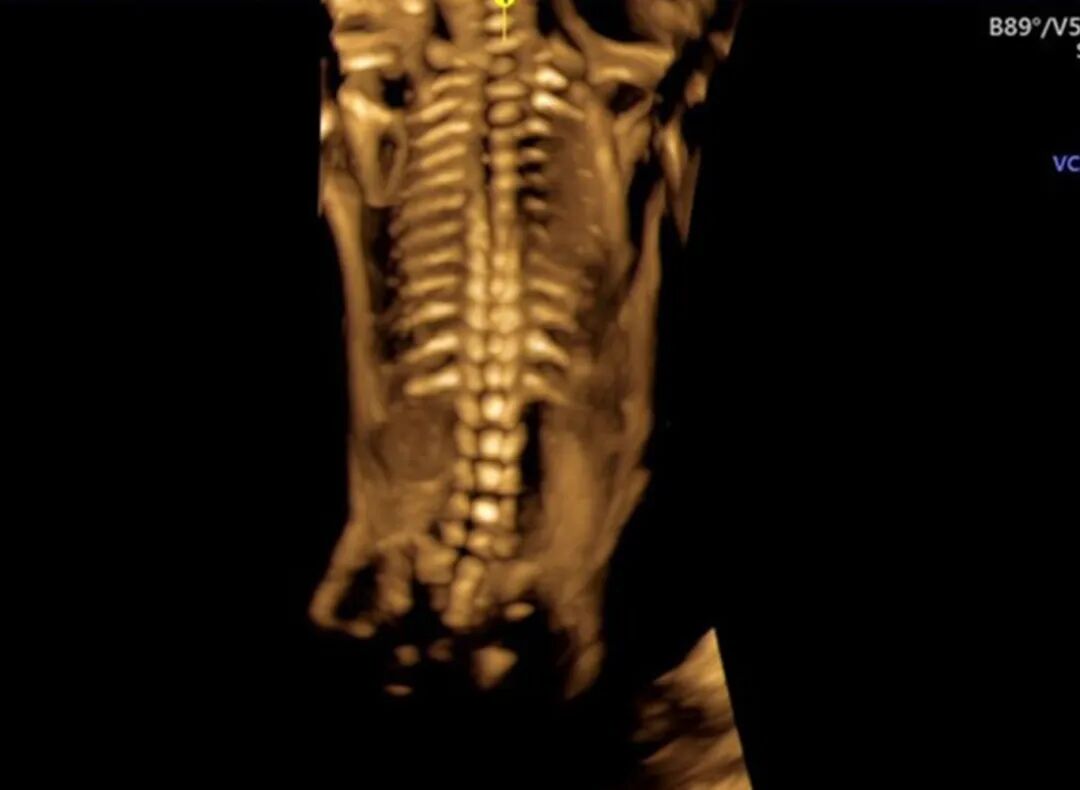

邱博士高清超声成像精彩画面(滑动查看更多)

邱博士特别擅长发现那些细微、复杂的高危疑难情况,尤其是胎儿复杂畸形结构。

许多隐藏很深的、容易被忽略的细微问题,在邱博士的超声探头下都能得到清晰的解读。

疑难复杂情况胎儿影像(滑动查看更多)